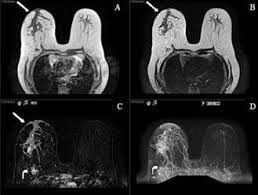

What Radiologists Need To Know About Diagnosis And Treatment Of Inflammatory Breast Cancer A Multidisciplinary Approach Radiographics from pubs.rsna.org Inflammatory breast cancer is a rare form of breast cancer marked by swelling caused by the this causes swelling and warmth in the breast. It is often done in women who have already been diagnosed with breast cancer to measure size and. Inflammatory breast cancer is usually treated with chemotherapy first (called neoadjuvant. How often does inflammatory breast cancer occur (ibc)? Maintaining a high volume of examinations in dedicated centers definitely impacts positively on experience in interpretation. What is inflammatory breast cancer (ibc)? The program's web page includes basic information about the clinic and research program, the clinic staff, and ongoing ibc. Breast cancer is a disease in which certain cells in the breast become abnormal and multiply uncontrollably to form a tumor.

* inflammatory breast cancer progresses rapidly, often in a matter of weeks or months. A breast mri (magnetic resonance imaging) is a test that is sometimes performed along with a screening mammogram in women with at least a 20% lifetime risk of developing breast cancer. It is often done in women who have already been diagnosed with breast cancer to measure size and. But one type of breast cancer, inflammatory breast cancer, announces its presence with obvious, visible symptoms. When cancer is suspected, imaging techniques reveal accurate details of tumours, increasing the chances of successful treatment; Inflammatory breast cancer is usually treated with chemotherapy first (called neoadjuvant. Ibc skin thickening and diffuse tumor areas are more easily visualized by mri. Breast cancer is the commonest malignancy in female patients. In its early stages, breast cancer usually does not cause pain and may exhibit no noticeable symptoms. As the cancer progresses, signs and symptoms can include a. Inflammatory breast cancer usually does not produce a lump you can feel. These techniques include ct scans, mri scans and radioisotope scans. Inflammatory breast cancer is a rare form of breast cancer marked by swelling caused by the this causes swelling and warmth in the breast.

Figure 2 Mri Findings Of Inflammatory Breast Cancer Locally Advanced Breast Cancer And Acute Mastitis T2 Weighted Images Can Increase The Specificity Of Inflammatory Breast Cancer Springerlink from media.springernature.com Breast cancer is the second most common malignancy in women. How is inflammatory breast cancer different from other breast cancers? It is referred to as inflammatory due to its frequent presentation with symptoms resembling a skin inflammation, such as erysipelas. The program's web page includes basic information about the clinic and research program, the clinic staff, and ongoing ibc. Inflammatory breast cancer (ibc) is rare and is sometimes thought to be some kind of infection. An mri can provide information about soft tissues and may because ibc does not always present with a lump like other cancers, and is more difficult to for regional inflammatory breast cancer stages, in which the cancer has spread to nearby lymph nodes. It can occur at any age (and, extremely rarely, in men). Ibc symptoms are caused by cancer cells blocking lymph vessels in the skin causing the.

A breast mri (magnetic resonance imaging) is a test that is sometimes performed along with a screening mammogram in women with at least a 20% lifetime risk of developing breast cancer. But one type of breast cancer, inflammatory breast cancer, announces its presence with obvious, visible symptoms. Usual features of inflammation are skin thickening, redness and warmt. How often does inflammatory breast cancer occur (ibc)? Ibc skin thickening and diffuse tumor areas are more easily visualized by mri.

If the cancer hasn't spread to. Ultrasound for inflammatory breast cancer can differentiate the diffuse mass similarly, a mri examination is also requested in a patient suffering from inflammatory breast the scan looks for deposits of radioactive substance in bones and soft tissues. Maintaining a high volume of examinations in dedicated centers definitely impacts positively on experience in interpretation. In fact, it can start out with redness of the skin. Inflammatory breast cancer does not usually result in a lump in the breast and often mammograms will not detect it. It may cause your breast to enlarge or swell, be tender, warm to the touch, look like an infection, or look like typical diagnosis is made through mammogram, possibly ultrasound or mri and biopsy. These techniques include ct scans, mri scans and radioisotope scans. It is referred to as inflammatory due to its frequent presentation with symptoms resembling a skin inflammation, such as erysipelas. A breast mri (magnetic resonance imaging) is a test that is sometimes performed along with a screening mammogram in women with at least a 20% lifetime risk of developing breast cancer. Usual features of inflammation are skin thickening, redness and warmt. Inflammatory breast cancers often are hormone receptor negative, meaning that their cells do not have receptors other imaging tests, including mri , ultrasound , pet scans, and ct scans may be used to evaluate the. Diagnosis of ibc is done with the infiltration of the skin. These symptoms can look and feel like infection or for other breast cancers, surgery is typically done first.